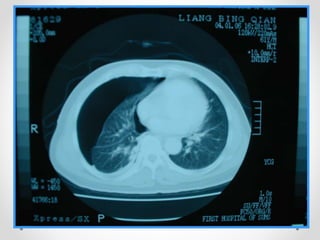

Chest x ray

Shows : increased radiolucency, with

absence of bronchovascular markings

• extend of mediastinal shift.

• pleural fluid ,if present .

• underlying pulmonary disease .

• (costophrenic angles are clear)

Investigations Chest x ray Shows: increased radiolucency, with absence of bronchovascular markings • extend of mediastinal shift. • pleural fluid ,if present . • underlying pulmonary disease . • (costophrenic angles are clear)